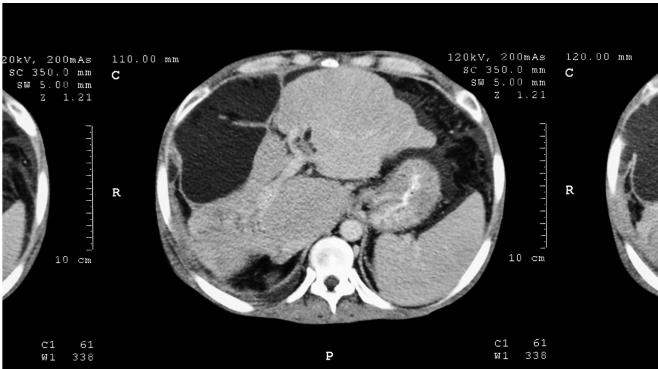

Большинство болезней печени приводит к тому, что клетки печени и печеночные дольки умирают. А поскольку печень является органом однородным, то все эти изменения происходят равномерно по всему органу. Одна клетка в левой части печени погибла, одна – в правой, одна – посередине, другие несколько клеток погибли в верхней части печени, еще несколько – в нижней части. В итоге получается картинка, похожая на мозаику. Если посмотреть на печень, то она в результате практически любой болезни становится не идеально гладкой, как была раньше, а приобретает диффузные, или размазанные, изменения. Выглядит это как рябь на воде или помехи на черно-белом телевизоре, такие «мурашки». Это типичные изменения в печени при всех воспалительных и большинстве инфекционных заболеваний. Их и называют диффузными изменениями печени в противоположность очаговым. Смотрите на рис. 60.

Рис. 60. Диффузные и очаговые изменения печени на КТ